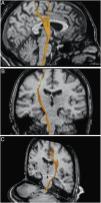

ResultsThe main bundles of the cortico-spinal tract and medial lemniscus were demonstrated and delineated throughout most of their trajectories, noticing their gross anatomical relation to one another and with other white matter tracts and grey matter nuclei the surround them, specially in the brain-stem; together with their corresponding representation on DTT images.

ConclusionsUsing the fibre microdissection technique we were able to distinguish the disposition, architecture and general topography of the cortico-spinal tract and medial lemniscus. This knowledge has provided a unique and profound anatomical perspective, supporting the correct representation and interpretation of DTT images. This information should be incorporated in the clinical scenario in order to assist surgeons in the detailed and critic analysis of lesions located inside the brain-stem, and therefore, improve the surgical indications and planning, including the preoperative selection of optimal surgical strategies and possible corridors to enter the brainstem, to achieve safer and more precise microsurgical technique.